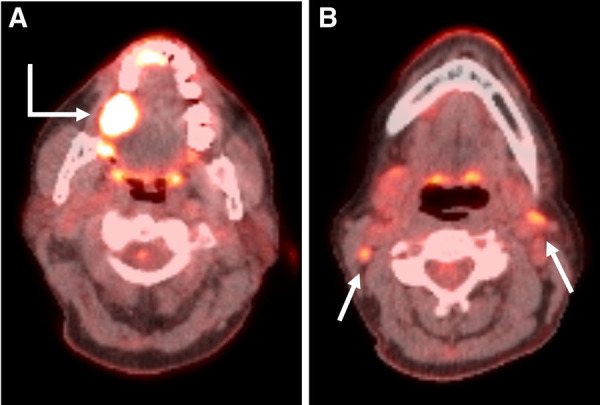

Abstract Image